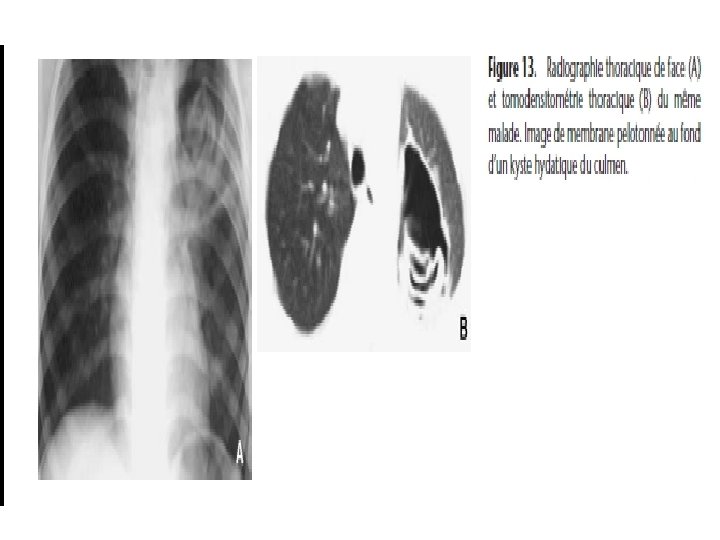

5) Kyste vomiqué: exclusivement radiologique (3 cas) - Image en grelot: opacité ronde au sein d’une cavité ronde - Image en cocarde: opacité ronde entourée d’une clarté en anneau - Image de membrane pelotonnée ou d’incarcération de membranes Lorsque le kyste est évacué en totalité, liquide et membrane, on peut avoir un aspect de guérison, avec ou sans cavité résiduelle; éventualité exceptionnelle.

Imagerie médicale